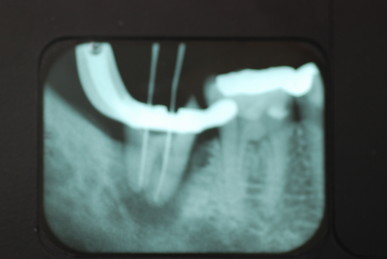

左下の一番奥の歯の治療がいい加減なようです。

左下の一番奥の歯の治療がいい加減なようです。しかし治療をしてみると滅菌しながら治療をすることの困難さを痛感しました。

三本ある根管の内、難しい手前の根幹の治療が為されていません。顎の骨に黒い影ができています。

根管治療終了です。

骨の部分は健康を回復しています。影がありません。治療が成功しています。